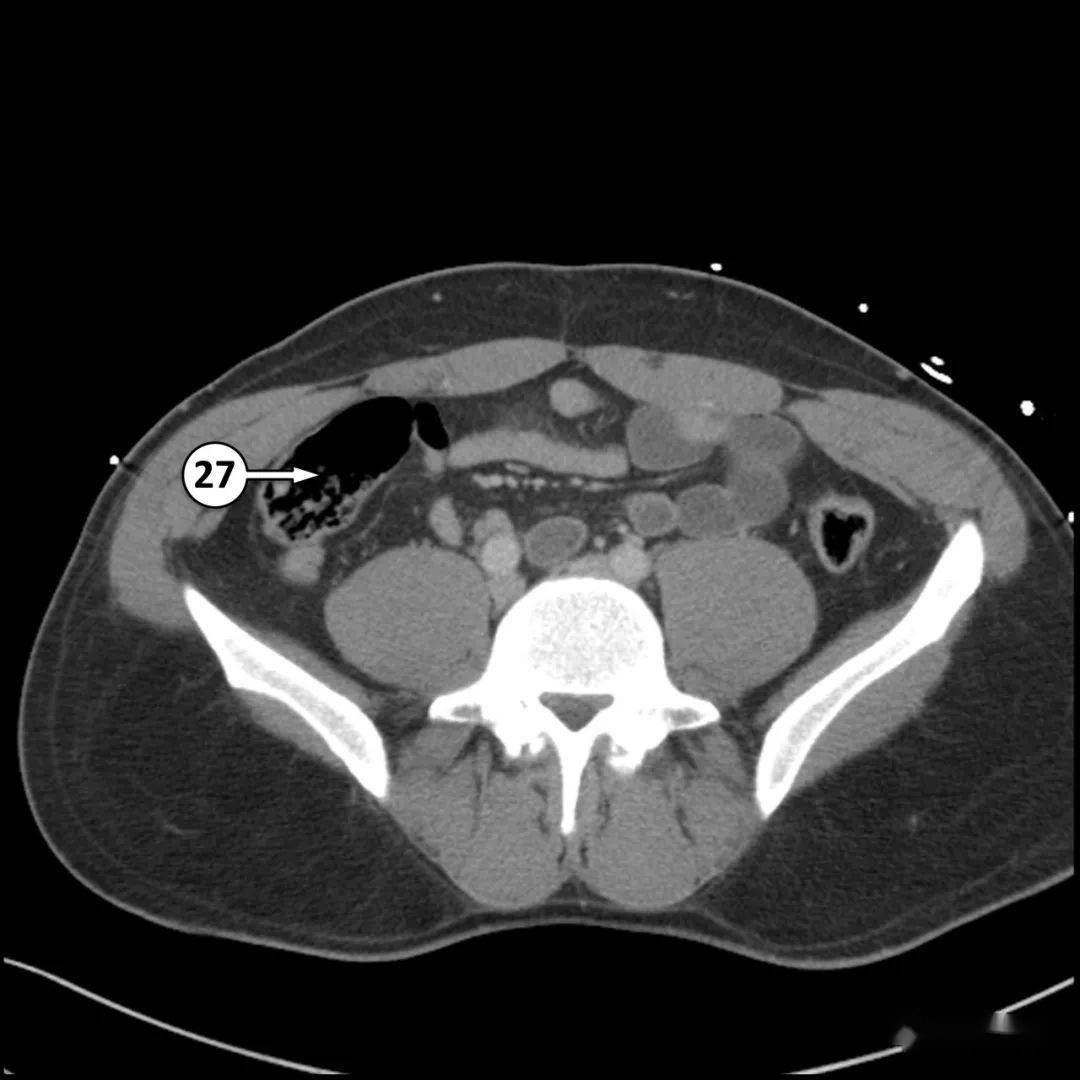

半月线疝

2,半月线疝(斯皮格尔疝),结肠经左侧腹直肌旁的腹壁缺口疝出,贴附于腹